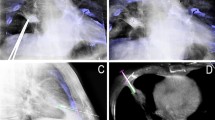

As the second step, the needle path was planned on the same workstation using commercially available software (Syngo iGuide, Siemens Healthcare). Figures 1, 2, 3 and 4 demonstrated this procedure for a 0.5-cm in diameter pulmonary lesion, and Figs. 5, 6, 7, and 8 demonstrated this procedure for a 2.0-cm in diameter pulmonary lesion. The reconstructed 3D volume was first loaded. In the orthogonal multiplanar images, the skin entry point and target lesion positions were manually selected and marked by a cross and a circle, respectively. A virtual path was then generated with its angulations and length calculated and displayed. All three multiplanar images were automatically aligned to the defined path to provide in-plane views (Figs. 2, 6). This procedure could be iteratively performed, modified, and reviewed until a satisfying path was obtained.

CBCT orthogonal multiplanar images with graphics showing planned needle path (yellow line) into target lesion (red circle) (a–c). The cross indicated the skin entry site and the circle indicated the target lesion site. The needle position relative to the anatomical structures was displayed in 3D using volume rendering technique (d)

The laser navigation system on the Flat-panel can quickly locate the needle point on skin, Thus the skin entry point could be determined (a). Real-time fluoroscopic images in bull’s eye view (b) and progression views (c). The needle was advanced along the planned needle path (dotted line) from skin entry site (white cross) to target lesion site (white circle). Sufficient tissue sample was obtained (d)

CBCT orthogonal multiplanar images with graphics showing planned needle path (yellow line) into target lesion (red circle) (a–c). The cross indicated the skin entry site and the circle indicated the target lesion site. The needle position relative to the anatomical structures was displayed in 3D using volume rendering technique (d)

In order to use the planned path to align the needle in actual 3D space, the virtual path was then projected and superimposed onto the live fluoroscopic images and displayed on a dedicated live monitor (Figs. 3b, c, 7a, b). The software automatically calculated the C-arm angulations, table motion, image zoom, and then controlled the C-arm moving to reach the desired position. First, the C-arm rotated to the Bull’s Eye View, where the C-arm was angulated in the way that the cross and the circle displayed on the live monitor completely matched and the central X-ray beam was aligned with the planned path (Figs. 3b, 7b). The laser navigation system on the Flat-panel can quickly locate the needle point on skin, Thus the skin entry point could be determined (Fig. 3a). The needle orientation was adjusted until both the tip and hub of the needle in the fluoroscopic image were superimposed and located at the centre of the circle and the cross. Second, after the skin entry point and needle orientation were determined, the needle was advanced under fluoroscopy until the planned target lesion position was reached. The C-arm was rotated back and forth to two different angles subsequently to monitor the needle progression. These two angles provided lateral views (progression view) of the planned needle path and helped to ensure that the needle was advanced along it (Figs. 3c, 7b). Third, a 3D scan was acquired to confirm the final position of the needle (Figs. 4, 8).